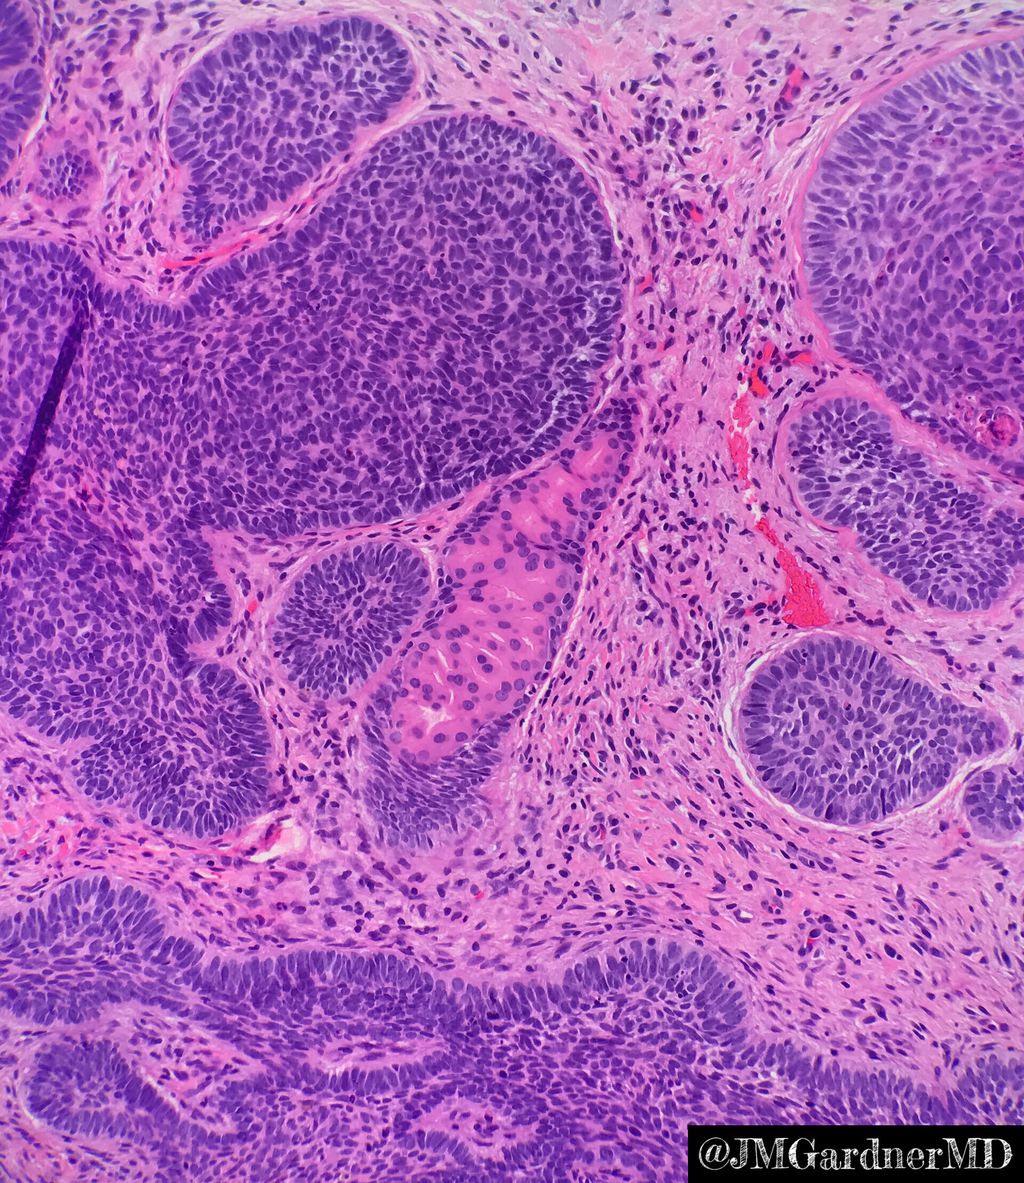

Recent changes to WHO classification of squamous intra-epithelial lesions of the head and neck discussed in this month's Arch Pathol Lab Med buff.ly/2KKKkAR

MARIBEL DONASTORG VITTINI Pembe Oltulu, MD The dx is T-cell lymphoblastic lymphoma. Not all starry sky pattern is Burkitt.